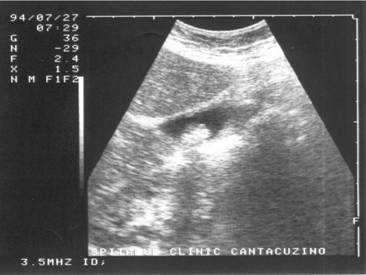

Figura 1. Vezica urinara

Figura 2. Chist renal stang situat in treimea medie

Figura 3. Chist ovar drept

Figura 4. Chist hepatic